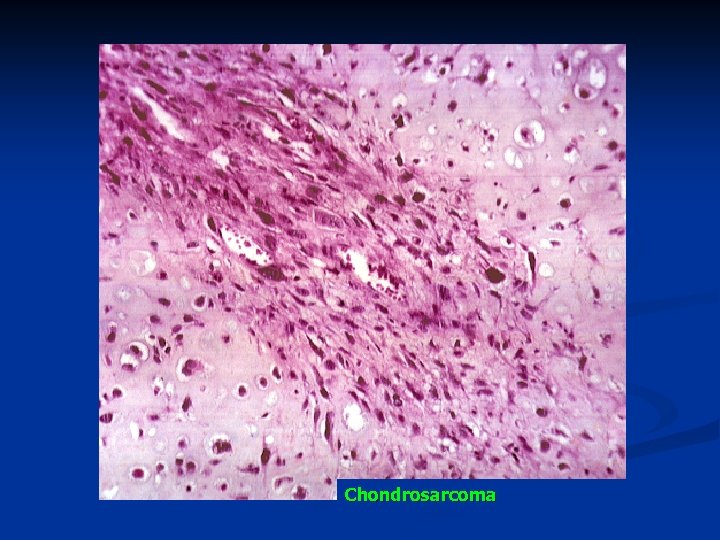

Chondrosarcoma

Chondrosarcoma

Chondrosarcoma

n Microscopy a lobular cartilaginous architecture, n highly cellular, n more than one nucleated cell per lacuna, n occasionally reveals tumor giant cells or clear cells, n with increasing grades of malignancy, has marked variation in nuclear and cellular size and shape. n

Chondrosarcoma